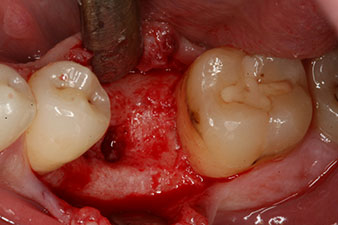

Fig. 1: Initial clinical situation after healing of extraction alveolus 36: The bone base is wide and there is sufficient keratinized gingiva.

A 28-year-old patient with a history of heavy smoking had to have tooth 36 extracted as a result of recurring apical periodontitis.

Due to the generally intact neighbouring teeth the only way to fill the gap was an implant.

incompletely ossified alveolus

Fig. 2: Six weeks later there was an incompletely ossified alveolus in the region of the mesial root.

However, six weeks after the extraction incomplete ossification was found after preparation of the mucoperiosteal flap in the region of the former mesial alveolus.